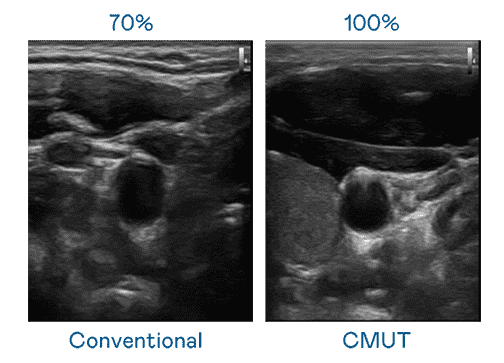

CMUT 技术是一种用电容式微机电元件来产生超音波讯号的技术。。。与传统 PZT 压电式技术相比,,,CMUT 频宽增加 30%,,更宽频的超音波讯号让影像解析度大幅提升,,,,是实现高影像品质医疗超音波扫描、、、促进精准医疗发展的关键技术。。。

大频宽带来超清晰影像

超音波影像的解析度高低,,,,首先取决于探头能发出的讯号频宽。。。。赏金国际 CMUT 可提供高清晰的超音波讯号,,提供高频宽、、高灵敏度、、、影像纹理细节更高的超音波影像,,,协助医护人员缩短影像判读时间及利用精准的医疗影像进行诊断。。